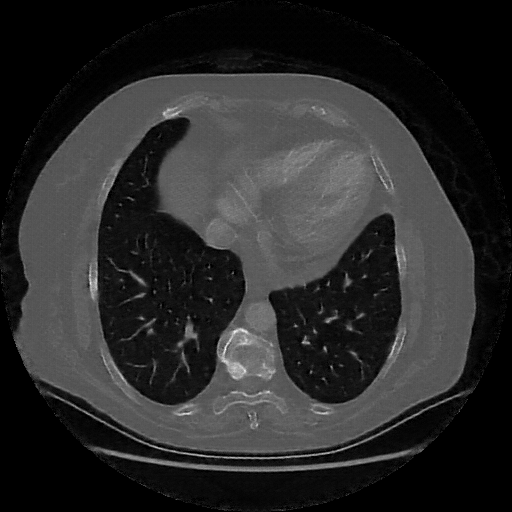

Targeted Slice 70 - Lung Window Analysis (Generated vs Real Venous)

0.747

Lung SSIM

92.5

Lung RMSE

41.3

Lung MAE

Average Lung Window Metrics Across All Slices (101 slices) - Generated vs Real Venous

0.731

Lung SSIM (Avg)

82.0

Lung RMSE (Avg)

39.1

Lung MAE (Avg)

Original VENOUS CT scan

Lung window (WL -600, WW 1500 β†’ Low βˆ’1350, High +150)

Generated VENOUS CT scan (A→B translation)